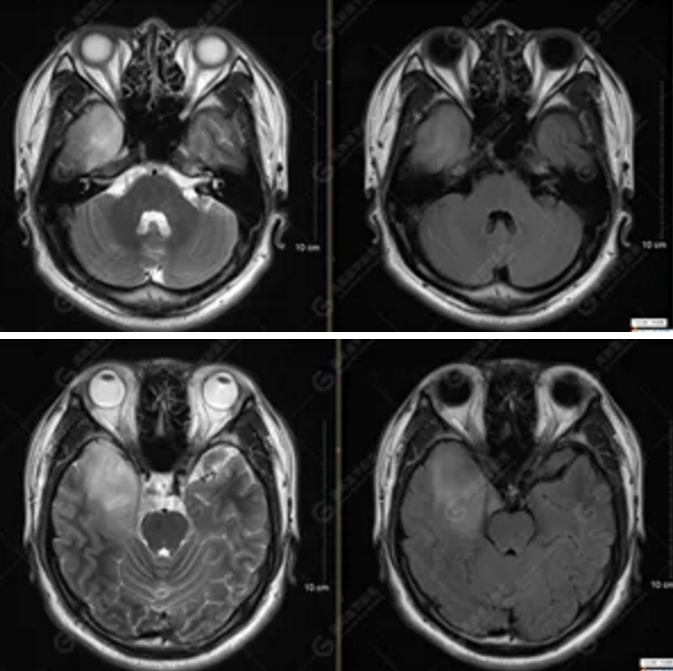

【MRI平掃及增強檢查所見】右側(cè)額顳島葉、右側(cè)海馬及右側(cè)基底節(jié)區(qū)見一團(tuán)塊狀異常信號影,累及右側(cè)下丘腦及視交叉,大小約5.1cm×4.5cm×4.3cm,呈長T1長T2信號,F(xiàn)LAIR序列呈等、稍高信號,DWI序列呈稍高信號,ADC圖高信號,增強后無明顯強化;病灶周圍見片狀長T1長T2水腫信號影,F(xiàn)LAIR序列呈高信號,病灶內(nèi)見右側(cè)大腦中動脈穿行。余腦實質(zhì)內(nèi)未見局灶性信號異常,增強后未見異常強化。右側(cè)側(cè)腦室輕度受壓,余腦室、腦池大小、形態(tài)均正常,中線結(jié)構(gòu)居中